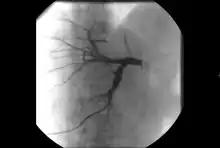

- Angiography: Imaging the blood vessels to look for abnormalities with the use of various contrast media, including iodinated contrast, gadolinium based agents, and CO2 gas.[3]

- Angiography: Sometimes referred to as traditional angiography, catheter angiography or digital subtraction angiography (DSA.) A small needle is inserted into a blood vessel, then exchanged for a catheter over a wire. The catheter is directed at the vessel to be studied, and contrast is directly injected to evaluate the lumen under video X-ray. This is an older technique than modern CT Angiography or MR Angiography, but provides unique advantages. With a catheter in place, provocative maneuvers can be performed such as breath holds or instillation of vasodilators, to evaluate a patient's blood flow dynamically. This can reproduce symptoms and identify functional abnormalities in a vessel that a static CT or MR imaging cannot.[79][80] Angiography provides the basis for all endovascular therapy.